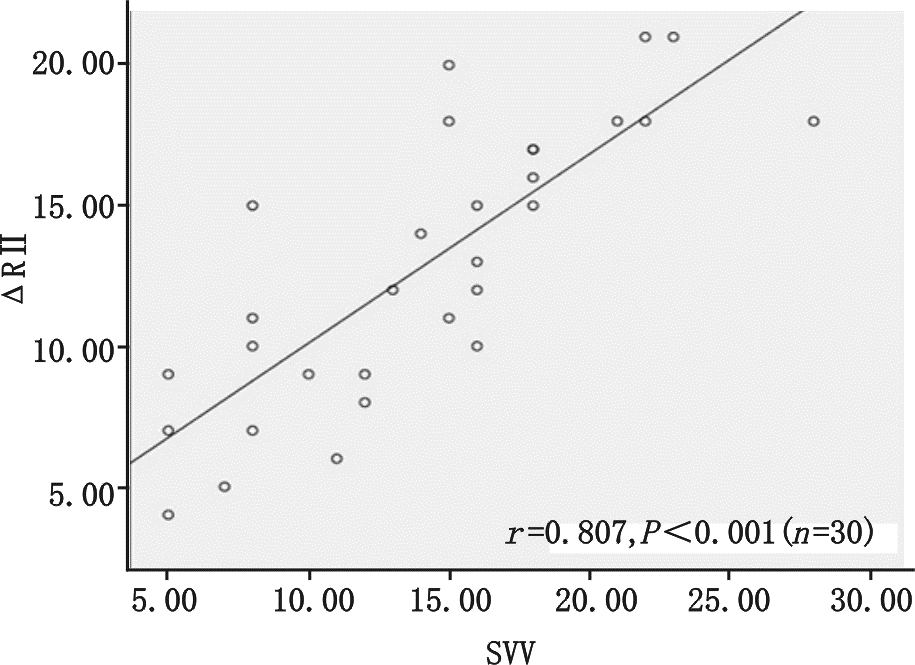

图 1显示ΔRⅡ随着呼吸周期显著的周期性变化,观察研究发现呼吸周期性ΔRⅡ与SVV呈正相关性(r=0.807,P<0.01见图 2),而呼吸周期性ΔR Ⅲ、ΔR AVF与SVV的相关性分别为(r= 0.453,P=0.016,r=0.642 ,P<0.01,分别见图 3、4);

| 图 2 呼吸周期性ΔRⅡ与每搏量变异的相关性 Fig 2 |

通过受试者工作特征(ROC)曲线评估ΔRⅡ与PPV预测SVV≥12%能力(见图 5),其曲线下面积(AUC)分别为0.910±0.055与0.865±0.076,两者比较差异无统计学意义。以ΔRⅡ临界值为11.5%预测SVV≥12%,其敏感度80%,特异度90%;

机械通气患者,吸气相胸腔内正压增大,导致右心回流减少,同时右心后负荷增加,致右心每搏量减少,经过两三个心动周期后左心室的前负荷减少,就这样左心室的每搏量随着呼吸周期波动,在吸气末每搏量达最大值,呼气末每搏量为最小值,这种现象在心脏Staring 曲线的上升支更明显,在平坦支就不明显,所以这种变异是反应心脏前负荷的指标[4, 13]。心电图R波幅度随呼吸周期性变化的理论基础是“Brody 效应”[7],即心脏内血液的电阻比心肌组织低,心脏内血液越多电阻越小,传导至身体皮肤表面的电量越大。基于心肺交互原理,机械通气吸气相正压通气挤压肺血管床使左室前负荷增加,左室容积增加,故在吸气末左室前负荷最大即左室容量最大,此时R波波幅最大,每搏量也最大,而呼气末R波波幅最小,每搏量也最小。实际上R波波幅从原理上代表的是心室内的血容量,每搏量是代表着从心室射到主动脉的血容量,两者是同源的,所以心电图呼吸周期性R波波幅变化与每搏量变异相关,且能反应血管内容量。研究表明V5、V6的R波受左室在胸腔内位置影响较大,而Ⅱ、Ⅲ、AVF导联R波基本不受影响[14, 15],故本研究选择ΔRⅡ、ΔR Ⅲ、ΔR AVF为研究对象,结果显示ΔRⅡ、ΔR Ⅲ、ΔR AVF与SVV相关,而且我们发现ΔRⅡ与SVV相关性最好,明显优于ΔR Ⅲ、ΔR AVF,与先前研究结果一致[14],这可能与Ⅱ 导联与正常心脏电轴最接近的原因相关。大量研究表明SVV ≥12%为预测容量反应性的阈值[5],本研究比较SVV≥12%组与SVV < 12%组的HR、CVP 、MAP、CI,均显示差异无统计学意义,但全心舒张末期容积指数(GEDVI)两组间差异具有统计学意义,说明预测容量方面GEDVI优于HR、CVP 、MAP、CI,但其监测需行PICCO,费用昂贵,且操作不便。笔者通过受试者工作特征(ROC)曲线评估ΔRⅡ预测SVV≥12%能力,其曲线下面积(AUC)为0.910±0.055(P<0.01),与PPV预测SVV差异无统计学意义。以ΔRⅡ临界值为11.5%预测SVV≥12%,其敏感度80%,特异度90%,说明在感染性休克机械通气的患者ΔRⅡ能准确反应或预测SVV值,虽然本实验未行容量负荷试验,但这给我们启示是否ΔRⅡ可作为SVV替代指标应用于机械通气患者辅助评估容量反应性,待进一步研究证明,进而开发应用ΔRⅡ这个新指标在心电监护仪上持续监测,如同PPV一样。

总之,机械通气的感染性休克患者,呼吸周期性ΔRⅡ与SVV有显著的相关性,可以准确预测SVV≥12%,可能ΔRⅡ如同PPV一样可以替代SVV准确预测容量反应性。由于本研究样本量不大,ΔR测量有误差,R波波幅改变的因素还有很多,比如心包积液[16],心肌缺血[17],QRS波电轴改变[18],心肌纤维本身的传导性[19]等,ΔRⅡ是否能直接评估患者容量反应性尚需进一步研究,进而为我们带来一个全新的动态血流动力学指标。